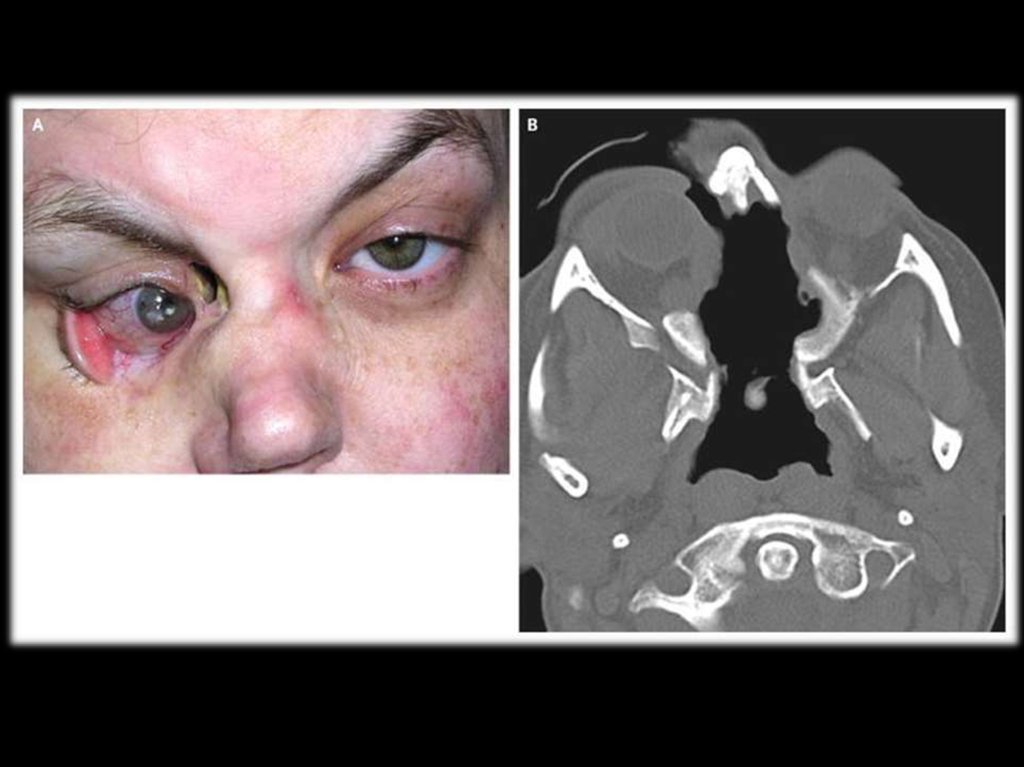

5.

Гранулематозные

синуситы

осложняются

вторичной

инфекцией.

часто

гнойной

Возможно разрушение хряща и костной

ткани

носовой

перегородки,

верхнечелюстной пазухи и орбиты с

формированием

“седловидного

носа”,

выбухание глазного яблока вперёд и вниз

(проптоз), деструкция тканей орбиты и

глазного яблока.